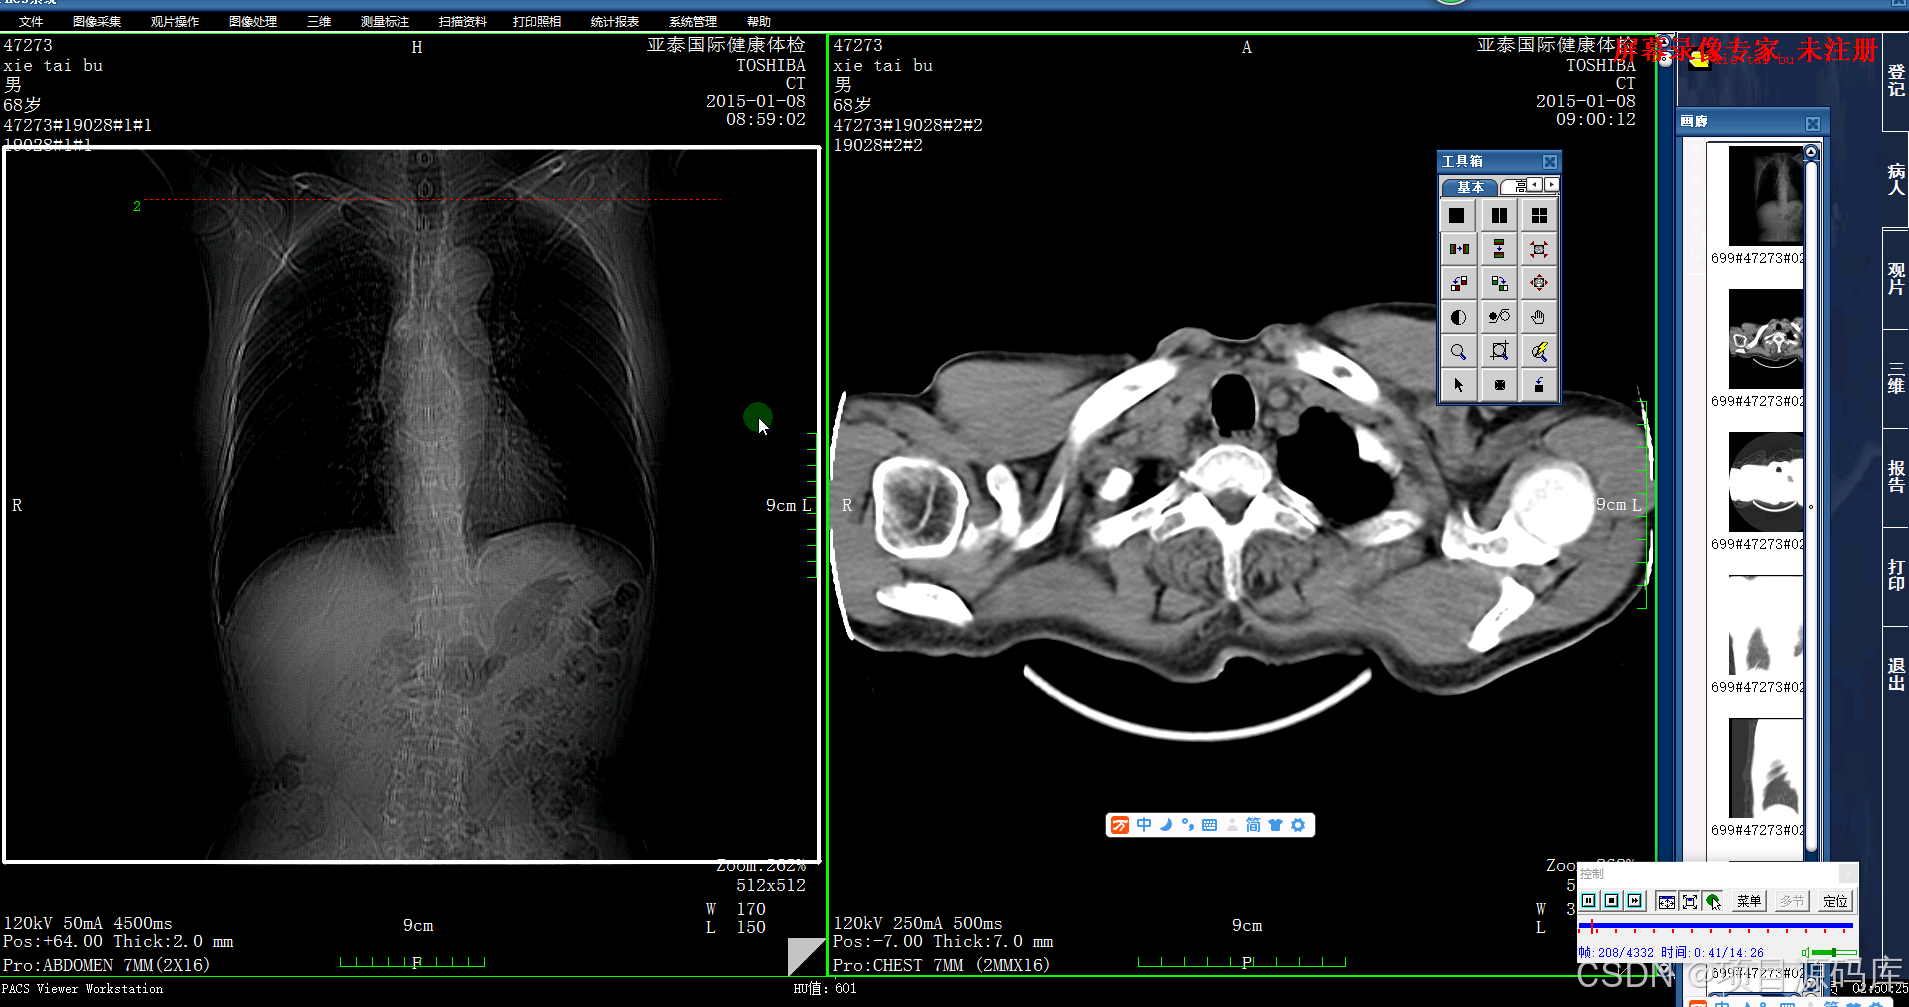

前端与可视化:Web技术 (Vue/React)、医学影像渲染引擎 (Cornerstone.js/VTK.js)、原生技术 (C++/Qt);直接面向医生的“门面”,决定了阅片诊断的效率和体验。

影像渲染引擎:这是Web PACS的技术核心。需要掌握专业的医学影像渲染库,如 Cornerstone.js (用于2D影像渲染和处理)和 VTK.js (用于MPR、VR等三维重建)。

传统C/S架构:部分对性能要求极高的诊断工作站可能仍会采用原生技术,如 C++ 结合 Qt 或 C# 的 WPF,以充分利用硬件资源 。